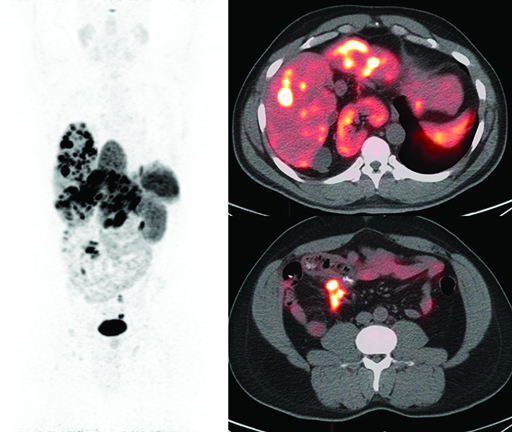

Neuroendocrine PET CTThe whole-body PET image (left) of a patient with a neuroendocrine tumor that has spread to the liver shows the tracer Gallium-68-DOTATATE binding to the tumor as dark spots, while the fused PET/CT images of the liver (top right) and lower abdomen (bottom right) show binding as white and orange spots.In conjunction with fMRI, performing a DTI scan—which tracks the movement of water—lets clinicians see the location of tracts of white matter in the brain. Disrupting these superhighways of information during a surgery can interrupt connections among areas of the brain involved in such vital functions as vision, movement, and reasoning.